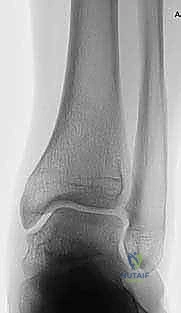

التشخيص الدقيق بالأشعة لتشوهات الكاحل

1. التخطيط الجراحي الدقيق (Pre-operative Planning)

يتم إجراء صور أشعة سينية خاصة (طويلة للساق بالكامل أثناء الوقوف) وأشعة مقطعية (CT Scan) ثلاثية الأبعاد. يقوم الدكتور محمد هطيف باستخدام برامج حاسوبية متقدمة لحساب الزاوية الدقيقة للتشوه، وتحديد حجم "الوتد العظمي" (Bone Wedge) الذي يجب إزالته أو إضافته لإصلاح المحور.